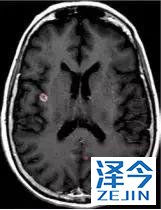

一位77岁的女性患有EPS15-NTRK1 IV期非小细胞肺癌,我们可以看到她的双肺满是病灶,并且出现了肝脏和脑转移,可以说是非常非常晚期了,

第3周期开始:

肺靶病变达到缓解,我们可以明显的看到前后的图像,病灶明显缩小了,

脑转移病变显示缩小了95%!

初始, 2018年6月 3周期 2018年8月